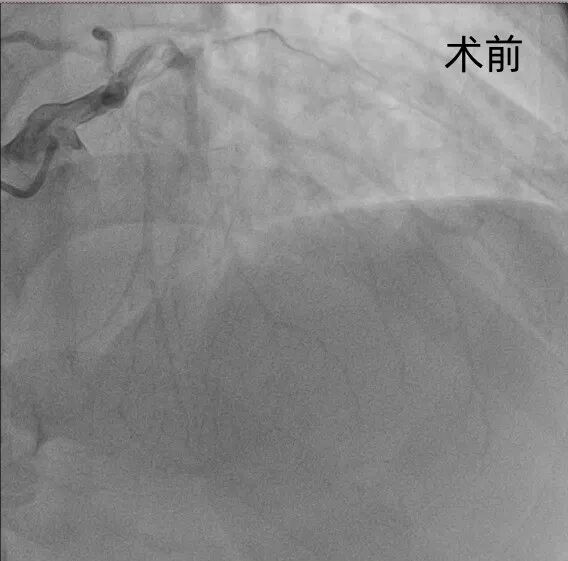

钟先生抵达医院后,直接送入导管室,冠脉造影清晰显示:前降支(LAD)近端完全闭塞,远端血流中断,心肌正处于“断供”坏死的危急状态。

心血管科团队当机立断,迅速实施PCI术,精准植入3枚支架,闭塞血管瞬间恢复通畅。从患者入院到血管成功开通,全程仅用46分钟,远优于国际指南60分钟的标准。